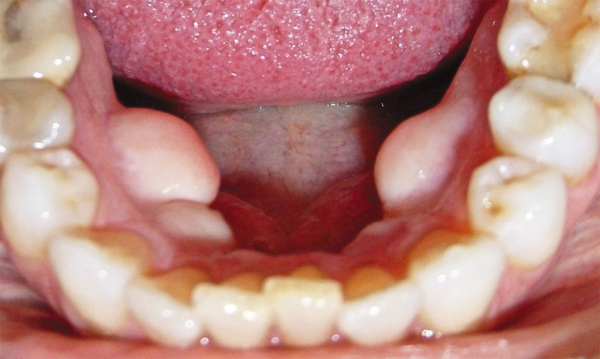

Одонтогенная

Опухоль такого рода связана с зубной системой. Это редкое доброкачественное фибробластическое образование, развивающееся из мезенхимальной зубной (дентальной) ткани. Встречается чаще у детей в нижней челюсти, отличается долговременным экспансивным разрастанием и появляется рядом с корнем либо около непрорезавшегося зуба. Длительный период никак себя не проявляет, но, достигая большого размера, приводит к деформированию челюсти. При попадании инфекции из расположенного рядом кариозного зуба случается воспалительный процесс.

Амелобластическая

Относится к типу одонтогенных фибром, иногда ее называют мягкая одонтома. Чаще встречается у молодых мужчин старше 20 лет, локализуется обычно в нижней челюсти и медленно растет. После удаления возможен рецидив. У этой опухоли есть злокачественная аналогия — амелобластическая фибросаркома, поэтому диагностике уделяется особое внимание.

Дольчатая

Вид этой опухоли в основном образуется в передней части ротовой полости на верхней челюсти. Значительно реже наблюдается внизу ротовой полости или рядом с альвеолярным отростком. Внешне выглядит, как рельефное бугристое образование. В большинстве случаев дольчатая фиброма вырастает из-за плохо закрепленного, обычно старого съемного зубного протеза, который натирает челюсть своими краями.